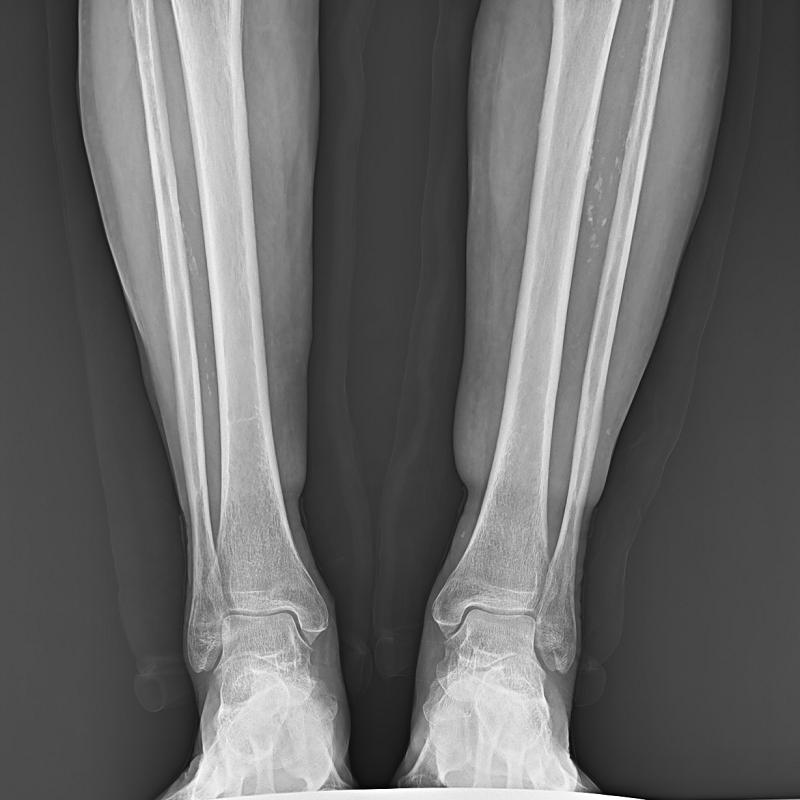

● 低位攝影

球管及胸片架可大范圍縱向移動(dòng),平板探測(cè)器中心最低離地35cm,輕松滿足膝關(guān)節(jié)、踝關(guān)節(jié)等低位攝影的要求。

● 圖像拼接

系統(tǒng)可以識(shí)別曝光圖像,無需設(shè)置識(shí)別點(diǎn)即完成精準(zhǔn)拼接,呈現(xiàn)大范圍完整影像。